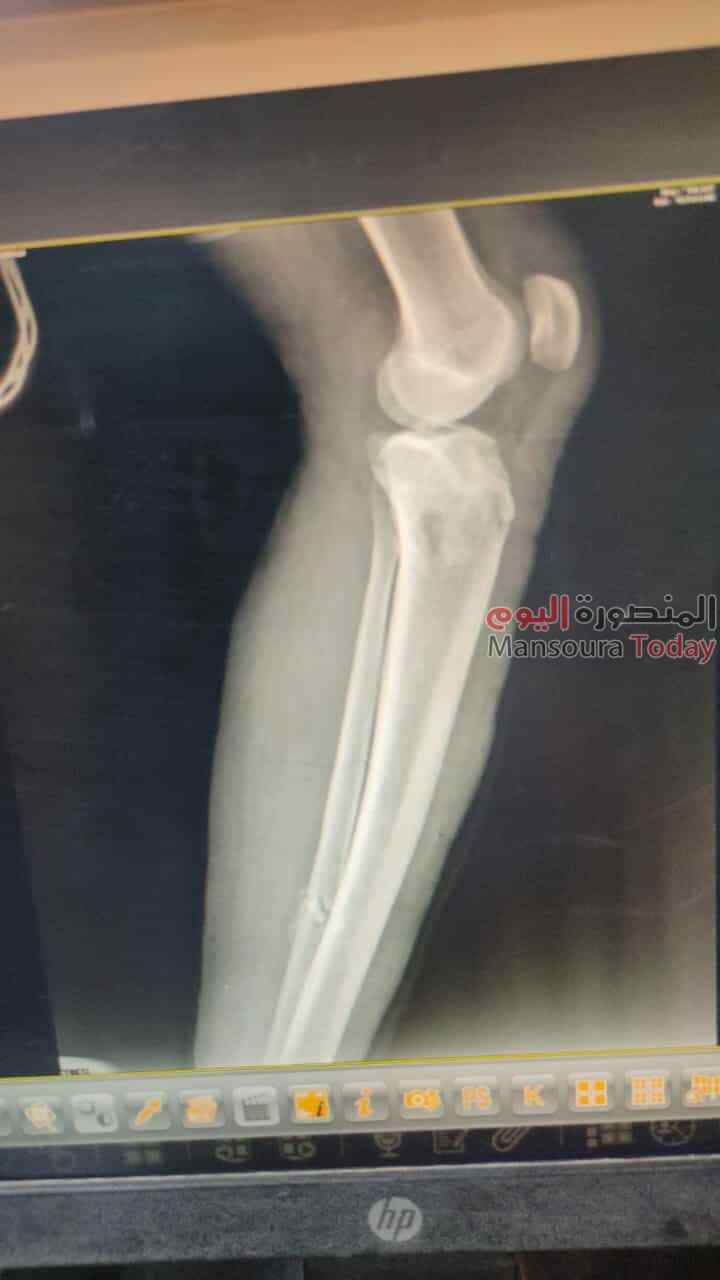

نجح فريق طبى مشترك من قسمى العظام وجراحة التجميل بمستشفى السنبلاوين العام في التدخل السريع لترقيع جلد الساق لمريض يعانى من كسرمضاعف بعد تركيب مثبت خارجي

وأوضح الدكتور تامر مدكور وكيل وزارة الصحة بالدقهلية أن الحالة تم تحويلها لمستشفى السنبلاوين وهى تعانى من كسر مضاعف مفتوح من الدرجة الثالثه بالساق اليسرى مع فقدان في الجلد و الانسجة حيث تم تثبيت الكسر بمثبت خارجي مع الحفاظ على وضع الكسور ورد العظام وعقب ذلك جرى ترقيع للجلد من خلال أطباء جراحة التجميل .